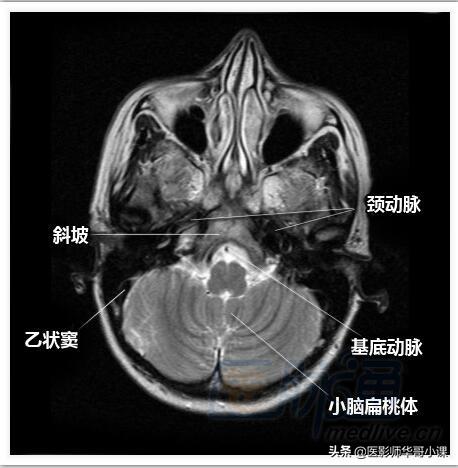

颅脑磁共振MRI解剖--轴位